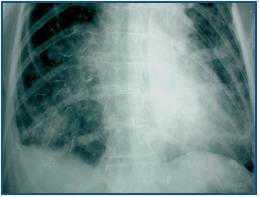

The case involves a 54-year-old female patient with a medical history of hypertension and chronic kidney disease, who had not followed a peritoneal dialysis programme for 8 months, and who was admitted to our department for diarrhoea with hypotension and an episode of rectal bleeding. The abdominal physical examination was irrelevant. The detailed findings showed hyperamylasaemia at around 900U/l (42-220U/l), with leukocytosis levels at 22.1 X 109 l. The other laboratory parameters were at a normal level. The peritoneal fluid was analysed, ruling out peritonitis. An X-ray of the abdomen (figure 1) showed diffuse opacifications in the colon, which corresponded to the lanthanum carbonate tablets introduced 2 months prior to hospitalisation as a treatment for hyperphosphatemia (0.75g oral 3/day). Two colonoscopies were carried out without success, showing a poor level of preparation and blocking the progression of the colonoscope. The presence of a fecaloma impacting on the rectosigmoidal junction was detected in an abdominal computed tomography. There were no signs of pathological masses in the pancreas or the rest of the abdomen. The fecaloma could be extracted; however, on the same day the patient showed signs of sudden dyspnoea and a deterioration of her general state, with hypotension and oxygen desaturation. The thorax X-ray (figure 2) showed radioopaque stripes along the pulmonary alveoli. The patient¿s family was further questioned, confirming the administration of the lanthanum tablets that had been suspended at admission. The patient underwent haemodialysis without any improvement in her pulmonary condition and died.

Figure 2.